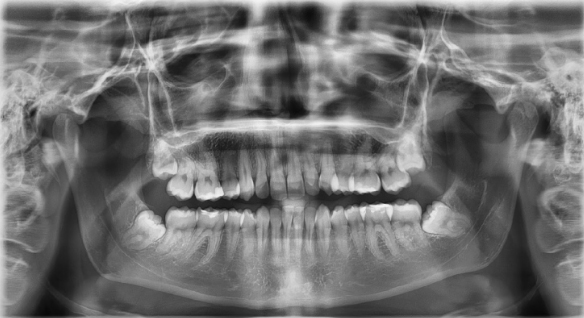

Zabieg usunięcia zawsze poprzedzony jest diagnostyką i oceną na podstawie zdjęcia rtg panoramicznego, które można wykonać w naszej klinice. Po dokonanej ocenie, chirurg znieczula miejscowo okolice ósemki. Jeśli ósemka jest widoczna gołym okiem, zabieg najczęściej jest prosty i niewiele różni się od zwykłej ekstrakcji. Jeśli jednak ząb jest ukryty zabieg jest bardziej skomplikowany, najczęściej też dłużej trwa. Po dokonanej ekstrakcji dentysta oczyszcza i zaszywa zębodół. W wielu przypadkach po ekstrakcji zęba zatrzymanego zalecane jest również podanie pacjentowi leku przeciwbólowych.